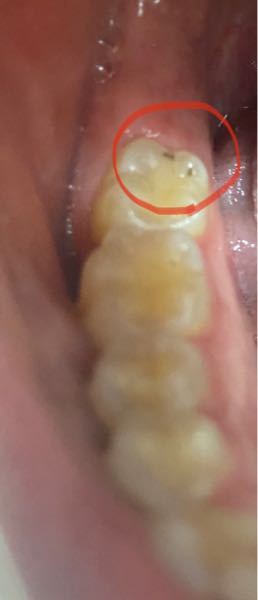

口の中の写真あります。 - これは虫歯ですよね?C1ですか?C2ですか

虫歯の写真、画像で見る進行度 ザ・ホワイトデンタルクリニック

象牙質の虫歯C2は痛くないがC2からC3への進行速度は速い!